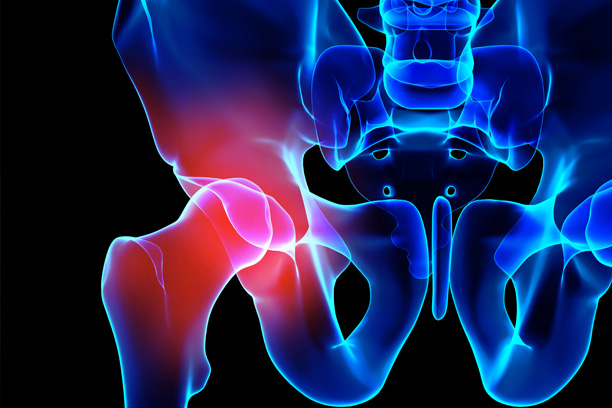

L’artrosi dell’anca, o coxartrosi, è generalmente causata dal naturale processo di invecchiamento e dalla degenerazione dell’articolazione, anche se nella maggior parte dei casi non si riesce a identificare una causa precisa. In alcuni casi l’artrosi può essere la conseguenza di traumi precedenti come fratture, di patologie sistemiche come l’artrite reumatoide o l’artrite psoriasica, di infezioni locali oppure di displasie congenite, cioè “malformazioni” presenti fin dalla nascita. Negli ultimi anni si è osservata una correlazione diretta con il fenomeno dell’impingement femorale.